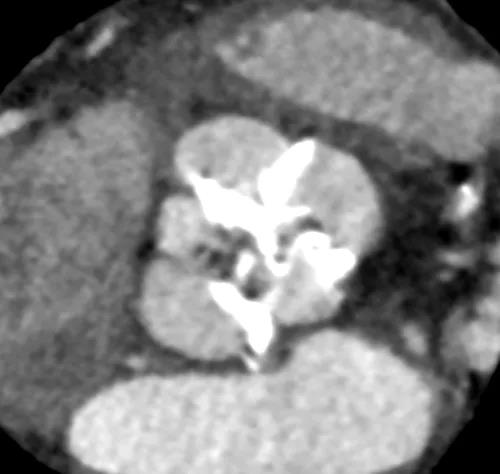

患者男性,67岁,头晕伴胸闷、胸痛6月余,术前心脏超声提示主动脉瓣增厚钙化伴重度狭窄,峰值流速4.9m/s,峰值压差94mmHg,平均跨瓣压差59mmHg,瓣口面积0.6cm2。CT显示主动脉瓣为Type I型二叶瓣,瓣叶边缘及左右冠瓣融合嵴严重钙化,致瓣口极度细窄。瓣环面积528.8mm2,测算直径25.9mm,左冠脉开口高度14.4mm,右冠脉开口高度17.5mm。患者合并重度肺气肿、多发肺大泡、支气管扩张,肺功能极差,静息状态下氧饱和度仅约80%,STS评分8.6%,属于外科手术高风险患者。

CT重建显示患者双侧髂动脉、股动脉、锁骨下动脉质量极差,多发钙化狭窄伴局部夹层,无法经股动脉和锁骨下动脉入路。而且患者重度肺气肿致心脏两侧受压,心尖被压缩在胸骨及肋弓骨性融合后方,亦无法经心尖入路。评估双侧颈动脉近端均有钙化斑块伴轻度狭窄,平均管径约6mm,左侧管径略大于右侧。颅内Willis环交通支通畅,可以耐受经单侧颈动脉介入手术。

主动脉瓣瓣环 Type I型二叶瓣

瓣叶及左右冠瓣融合嵴重度钙化 重度肺气肿、多发肺大泡

髂动脉、股动脉状况极差

颈动脉评估